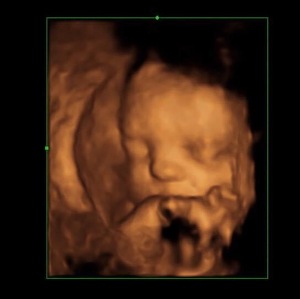

Lydie's Loop: Steps Against Stillbirth 2023